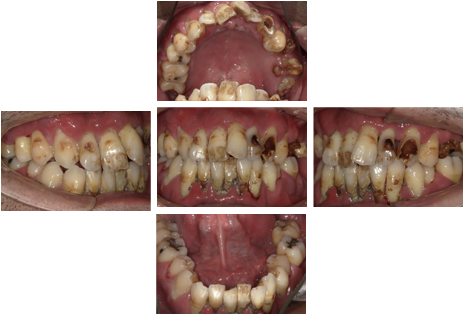

• CASE 5

Before

患者情報

40代男性

治療期間

約6カ月

総治療費

4,100,000円(税込)

治療内容

重度の虫歯と歯列不正、歯周病があり、すべての歯を抜歯し、上顎はインプラントを6本入れ、ALL ON6、下顎はインプラントを2本入れ、インプラントオーバーデンチャーにして治療しています。

リスクと副作用

外科手術により、術後数日間、腫脹や疼痛を伴うことがある。